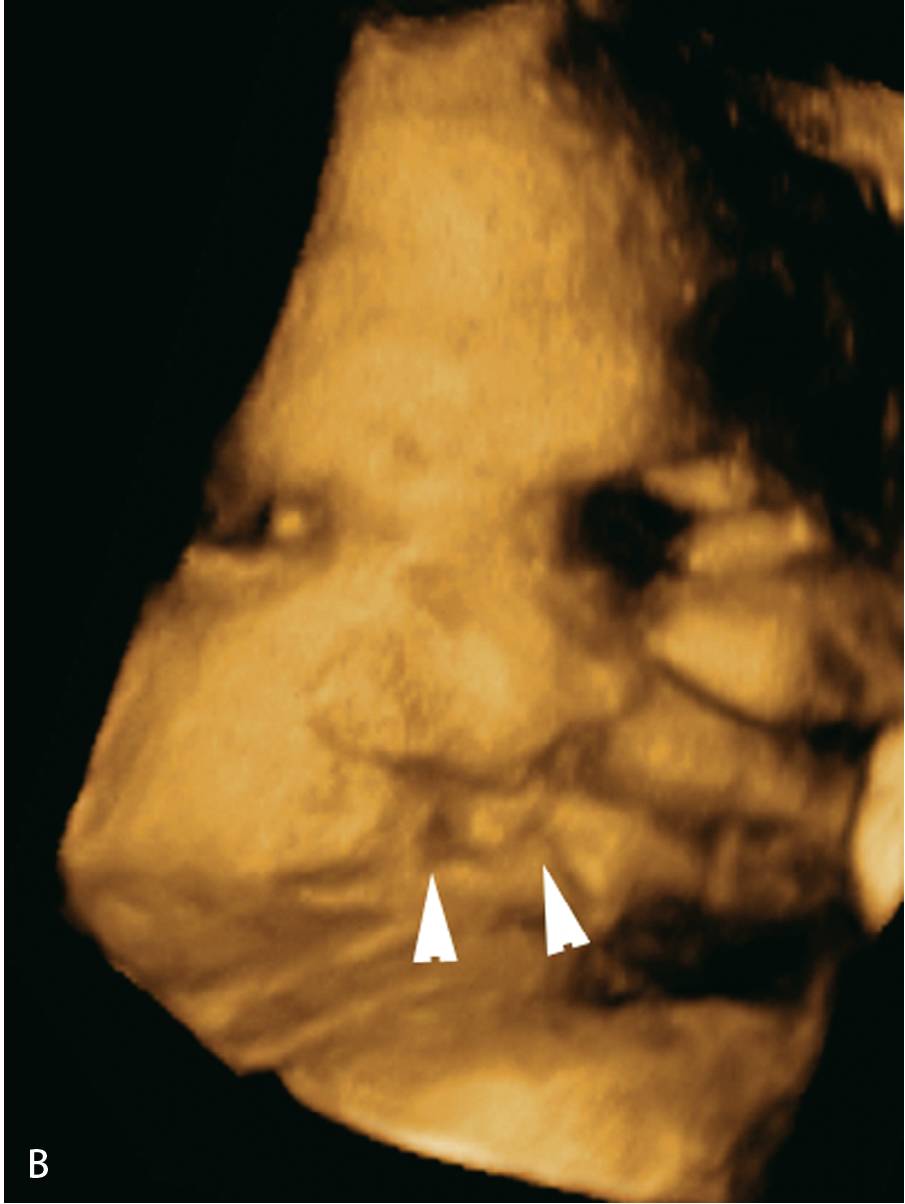

1.5正中唇裂.(c,d)三维图像示正中唇裂(箭头)延伸至鼻.